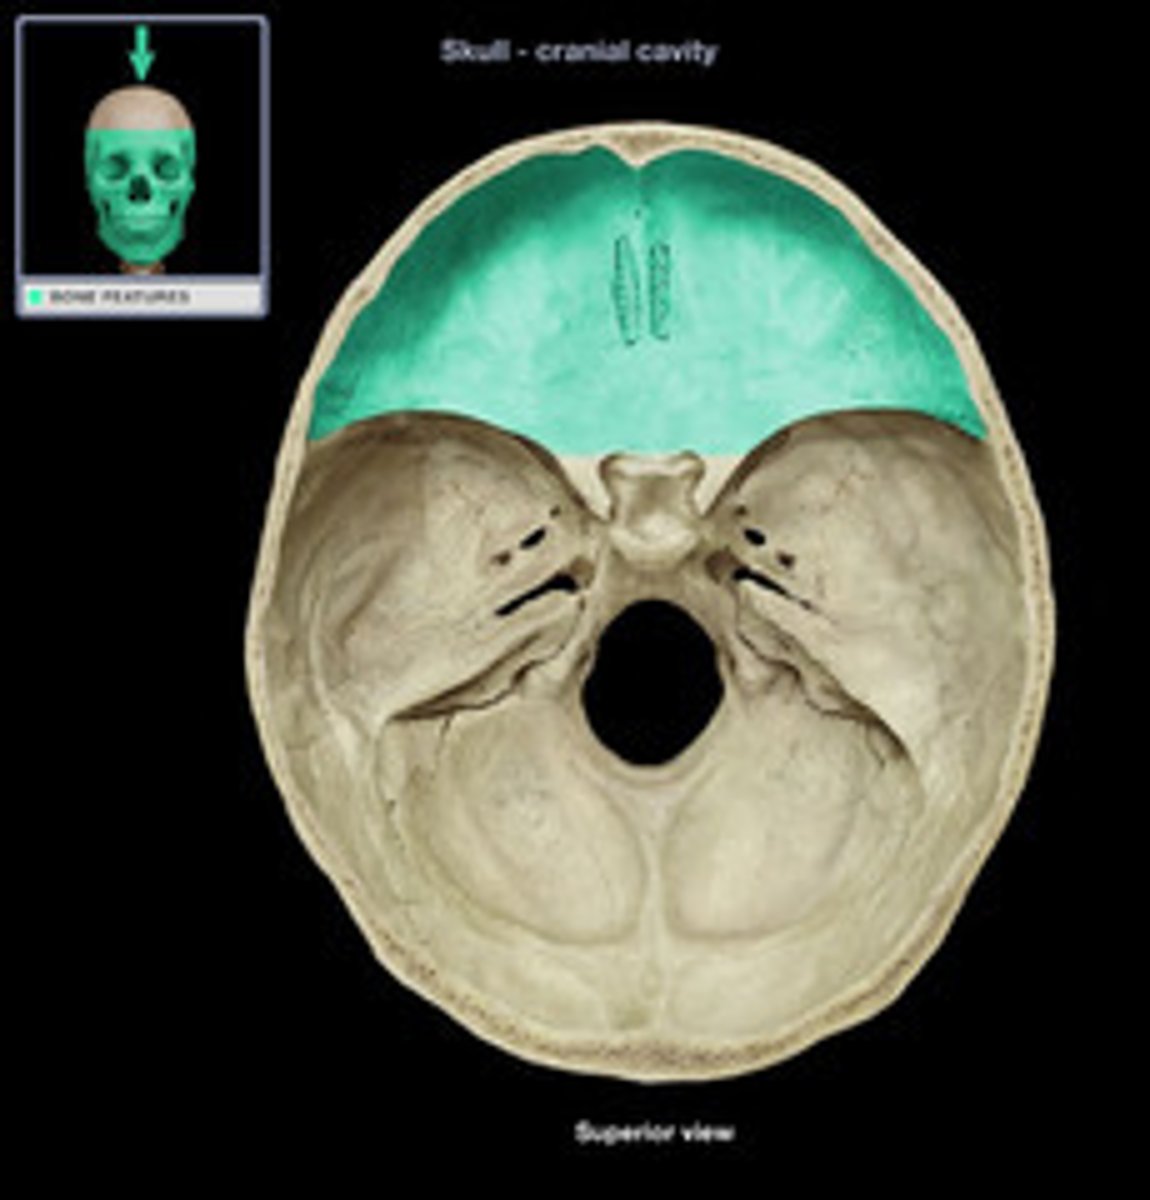

anterior cranial fossa

part of the cranial fossa that contains openings for olfactory and ethmoidal structures & supports the frontal lobes

1. ethmoid

2. frontal

3. lesser wing of sphenoid

what 3 bones make up the anterior cranial fossa?